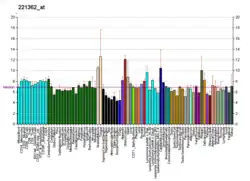

5-Hydroxytryptamine (serotonin) receptor 5A, also known as HTR5A, is a protein that in humans is encoded by the HTR5A gene.[5][6] Agonists and antagonists for 5-HT receptors, as well as serotonin uptake inhibitors, present promnesic (memory-promoting) and/or anti-amnesic effects under different conditions, and 5-HT receptors are also associated with neural changes.

The gene described in this record is a member of 5-hydroxytryptamine receptor family and encodes a multi-pass membrane protein that functions as a receptor for 5-hydroxytryptamine and couples to G proteins, negatively influencing cAMP levels via Gi and Go.[7] This protein has been shown to function in part through the regulation of intracellular Ca2+ mobilization.[5] The 5-HT5A receptor has been shown to be functional in a native expression system.[8]

The neurotransmitter serotonin (5-hydroxytryptamine, 5-HT) has been implicated in a wide range of psychiatric conditions and also has vasoconstrictive and vasodilatory effects.[5]